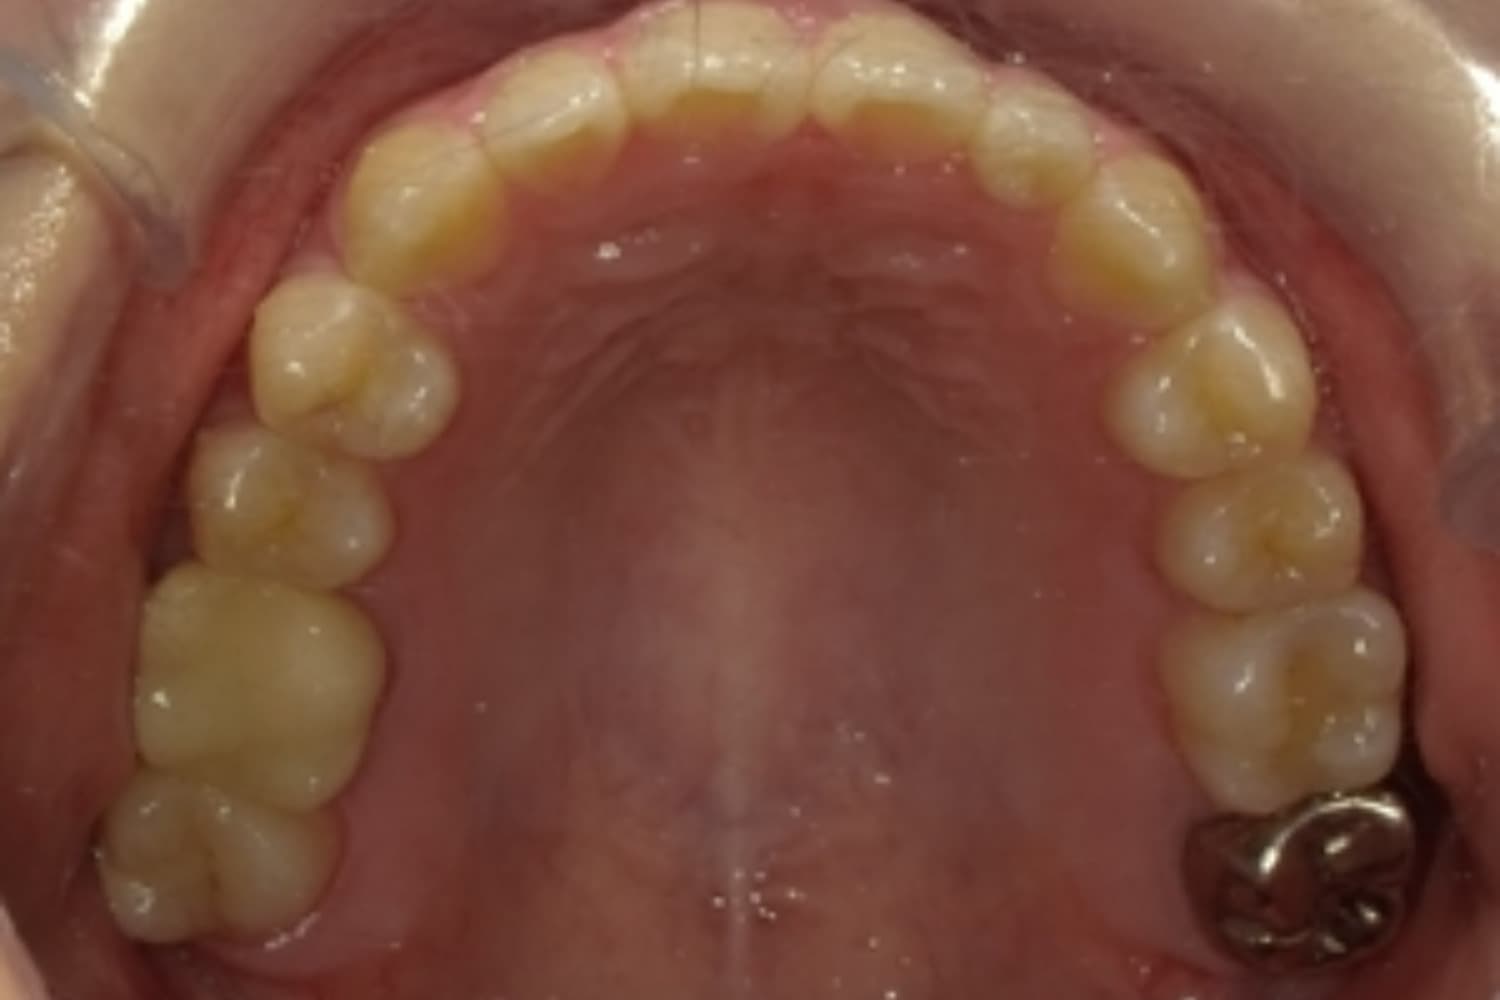

すきっぱ(空隙歯列)2

Before

After

気になる前歯の隙間と前歯のガタガタをマウスピース矯正(インビザライン)にて治療

治療期間

1年

費用

88万円(税込)

副作用・リスク

・矯正治療による歯の動きには個人差があり、想定より治療期間が延びることがあります。 ・矯正治療で歯を動かす際に痛みをともなうことがあります。 ・指示された通りに保定装置を装着しないと、歯並びや噛み合わせの後戻りを引き起こす可能性があります。